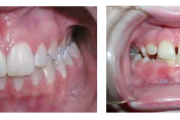

Koonilise kujuga lisahammas ülemiste tsentraalsete lõikehammaste vahel.

Suulaepoolt lõikunud koonilise kujuga lisahammas